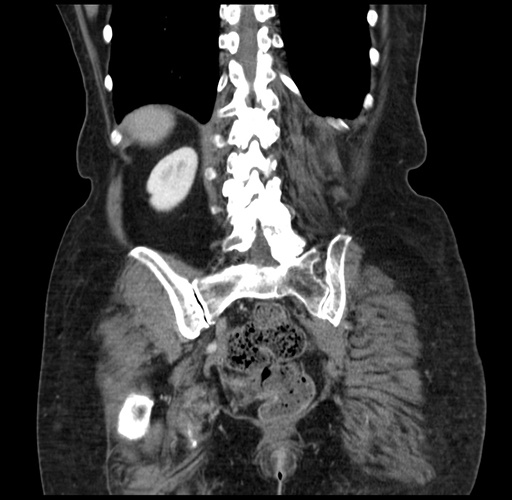

Pre-Chemo: Coronal Venous

Coronal Venous